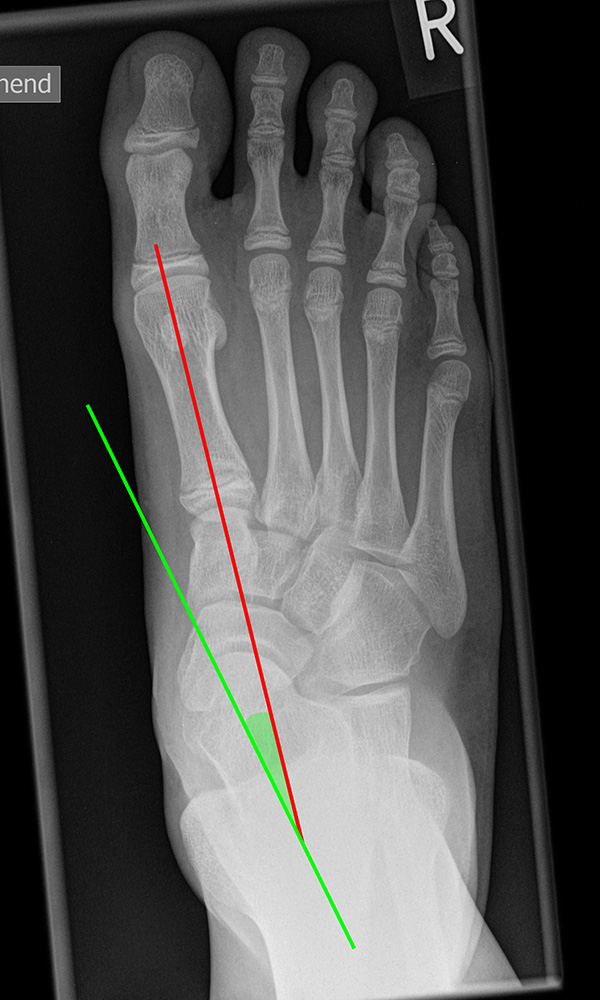

Vermessung der belasteten Aufnahmen des Fußes

Winkelmessungen am Fußskelett beziehen sich sämtlich auf belastete Aufnahmen 6. Die folgenden Aufnahmen zeigen die üblicherweise verwendeten Winkelmaße und ihre Definition. Viele Fehlstellungen des Fußes betreffen den Vor- und Rückfuß. Dies sollte bei der Beurteilung der Bilder und der Therapieplanung stets berücksichtigt werden.

Beurteilung eines Metatarsus adductus

Medial wird eine Linie von der medialen Begrenzung des TMT1-Gelenks und der medialen Begrenzung des Talonavikulargelenks (TN) gezeichnet. Auf der lateralen Seite des Fußes wird eine zweite Linie von der lateralen Begrenzung des Calcaneocuboid-Gelenks (CC) zur lateralen Begrenzung des TMT5-Gelenks gezeichnet. Die Mittelpunkte beiden Linien werden verbunden (blau). Der Winkel zwischen der Achse des Os metatarsale II (rot) und dem Lot auf Verbindungslinie (grün) ist ein Maß für die Stellung des Vorfußes zur Fußwurzel. Dieser Wert dient zur Charakterisierung eines Pes adductus. Ein Pes adductus kann zu einem normwertigem Intermetatarsale I/II Winkel führen, obwohl klinisch eine ausgeprägte Hallux valgus Deformität vorliegt 8. (Norm: ±13° 9.